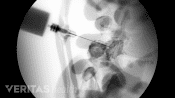

The physician uses X-ray guidance, called fluoroscopy, to direct a small needle into the facet joint. Contrast dye is injected to confirm that the needle is positioned correctly in the facet joint and that medication is contained inside the joint.

Following this confirmation, a mixture of anesthetic, such as lidocaine, and anti-inflammatory medication, such as cortisone, is then slowly injected into the joint.